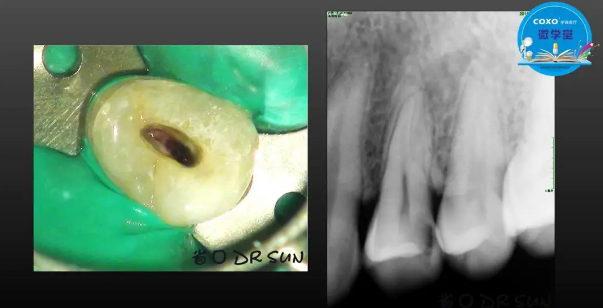

主任醫(yī)師,牙體牙髓副主任, 廣東省口腔醫(yī)院牙體牙髓科 主任醫(yī)師。2003年碩士研究生畢業(yè),研究方向為牙體牙髓病學,擅長于牙體牙髓病的診斷、齲齒、牙髓炎、根尖周病的治療以及前牙美容修復。